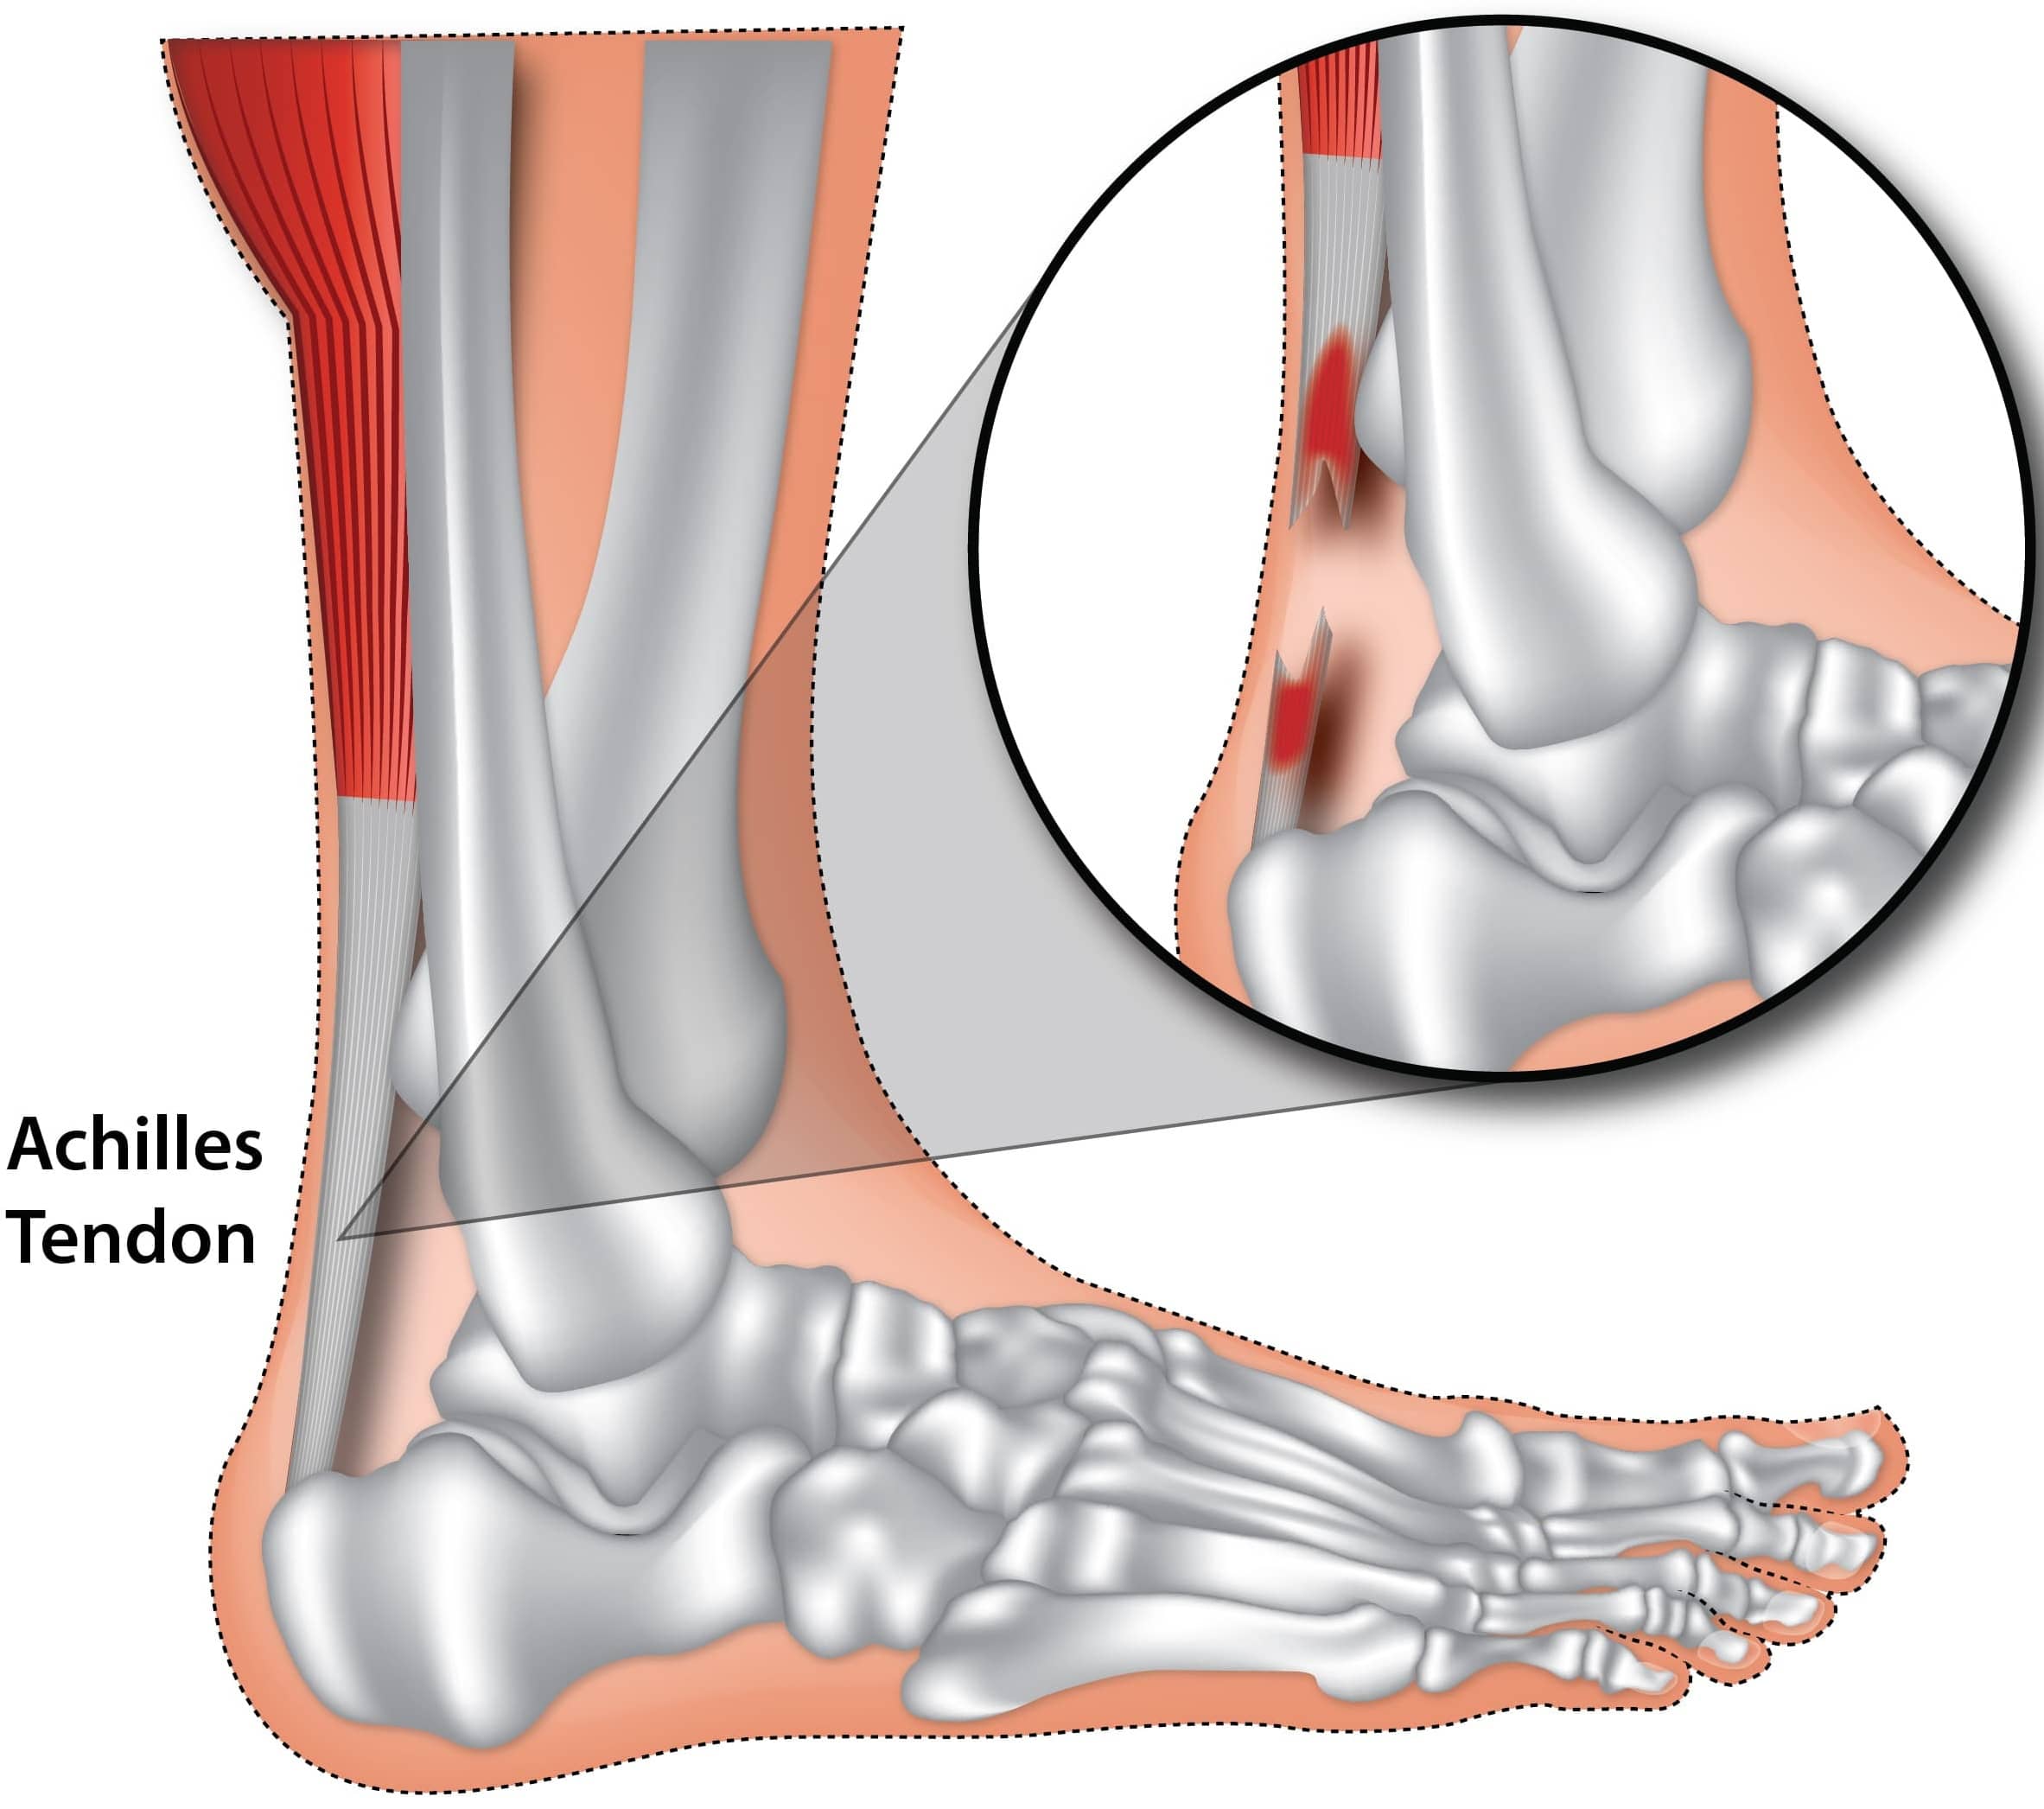

pictures of achilles tendon

Achilles Tendon Injuries – Active Care

Achilles Tendon Pathology – Radsource

Achilles Tendon Pain and Injury

Common Injuries of the Achilles Tendon – Osteopathy Singapore

Achilles Tendon Pathology – Radsource